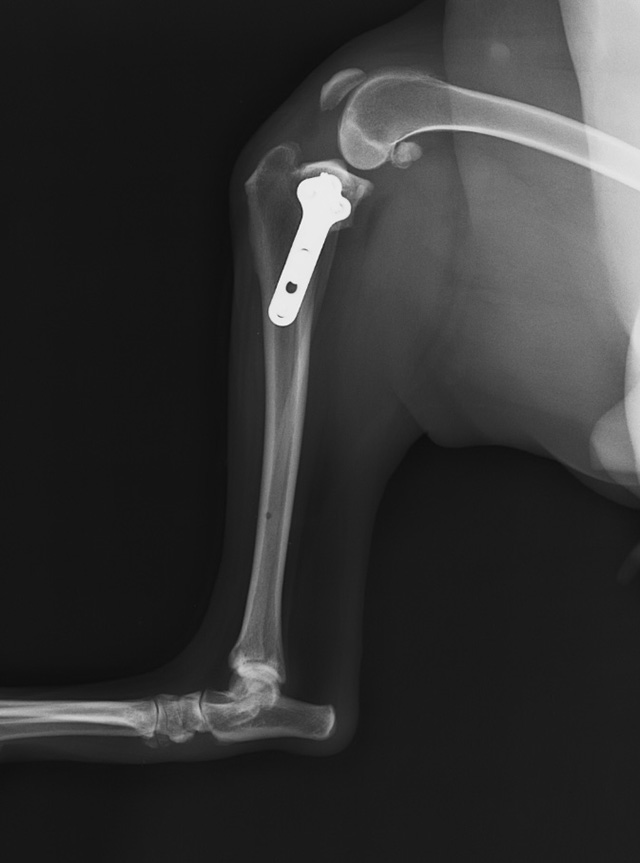

膝の靭帯が切れてしまい、足を地面につけなくなる病気です。当院では、二次診療施設での経験を活かした的確な触診とレントゲン検査で診断を行います。症状に応じた内科治療のほか、外科手術が必要な場合は、より安全で確実な実施のために高度医療施設(二次診療施設)へのスムーズなご紹介を行っています。

「より早く、より安全に」治すことを最優先に考え、専門性の高い外科手術(TPLO等)が必要な場合は、信頼できる二次診療施設へ迅速にご紹介します。手続きだけでなく、場合によっては施設への送迎もサポートしており、診断から完治まで責任を持って見守ります。